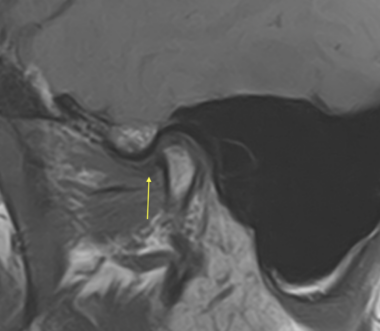

これは顎関節の MRI 画像です。歯科医院の矯正治療、また噛み合わせ治療で撮影することが一般的でないためご覧になったことが無い患者さんもいると思います。ただし顎関節の軟骨の状態を確認するためには MRI は必要なものです。皆さんも股関節、膝関節、肘関節で外傷や痛みがあったときに当然 MRI の精密検査があるはずです。こう考えると顎の「関節」の治療だけレントゲンや CT のみで済ませてしまう不誠実さを実感頂けると思います。

左側の顎関節画像の黄色い矢印は軟骨です。画像診断(読影)をすると顎関節に載っているはずの軟骨が前方にズレでいることがわかります。このように前方にズレることで、咬み合わせに影響が表れます。ただし歯科医院で一般的なレントゲンや CT は原則的に固いもの(骨)を映し出す検査機械ですので、軟骨や筋肉などの軟組織を正しく映し出すことができません。そのために顎関節治療では MRI が不可欠なのです。